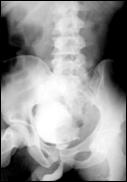

4.5. Radiografia osoasa 4. Radiografia toraco-pulmonara

Figura 44. Metastaza in articulatia coxo-femurala

dreapta Figura 45. Metastaze pulmonare multiple dintr-un carcinom vezical

4. Scintigrama osoasa

Cele mai multe metasteze la distanta, provocate de tumorile vezicale maligne, sunt localizate in plamani si in oase. Diagnosticul acestora se face prin: radiografii toraco-pulmonare, radiografii osoase sau scintigrame osoase (care evidentiaza metastazele osoase cu 9 - 12 luni mai devreme decat expresia evidenta a acestora pe radiografiile standard).